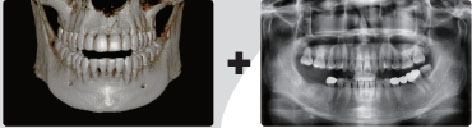

O scanare cu PaX-i3d Smart nu vă oferă doar o imagine CT, dar şi o imagine Auto Pano.

Acest lucru înseamnă că pacienţii care au nevoie de ambele imagini nu trebuie să fie supuşi la două scanări cu raze X. De asemenea, imaginile CT şi Auto Pano sunt afişate concomitent - One Viewer, în acelaşi ecran în software-ul Ez3D-i V4.0.

*Imaginea 2D – Pano este reală, nu reconstituită soft din CT !!!

[3D și 2D în One Viewer]

Vizualizarea imaginilor 2D si 3D împreună oferă multe beneficii. Nu este nevoie să se utilizeze două programe diferite ci One Viewer le prezintă sub un aspect profesional pentru pacienţii dumneavoastră.